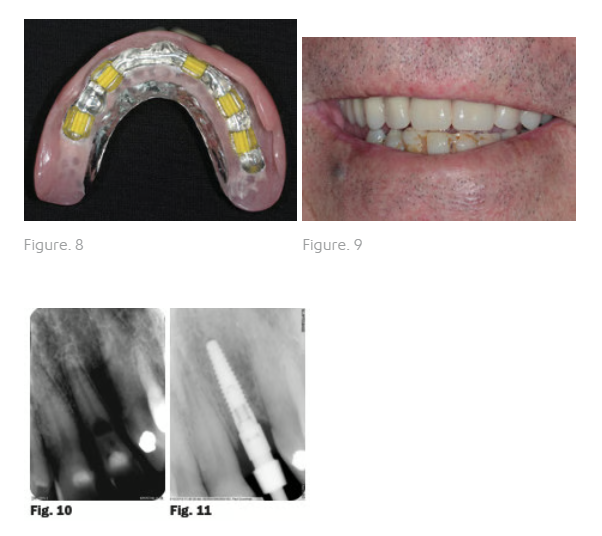

An excellent result was obtained (Fig. 7). On confirmation of passive seating of the bar, an acrylic/ wax plate was made using three implants as an anchor point. This enabled a precise interocclusal registration to be carried out. The laboratory then finished the case by make a Co-Cr upper full denture without any palatal coverage. The milled bar was torqued down to the 30Ncm level and the plate inserted over it (Fig. 8). Excellent retention and aesthetics were obtained (Fig. 9).

A healthy 65 year-old male presented to the surgery with the chief complaint of a loose front tooth which was uncomfortable upon chewing and with pressure. A radiograph revealed significant bone loss around tooth 22 in addition to the focalised loss of internal tooth structure in the mid-third of the root (Fig. 10). The root was almost perforated. Clinical examination revealed Class III mobility. No drainage point or fistula were noted. A diagnosis of internal resorption was given due to the focal point of radiolucency within the pulp chamber area. Due to the extent of the defect and the advanced bone loss, tooth removal was advised.

Nobel Biocare Replace Select Narrow platform was selected by the oral surgeon which was placed in the position of tooth 22 under local anaesthetic. Bone quality was good and the implant was seated to 35Ncm. The implant was placed and a screw-retained restoration was planned. The implant was submerged during the healing phase and the removable partial denture was adjusted. The periodontist placed a 5mm healing abutment. Possible minor soft tissue augmentation was to be evaluated at that time. An appointment was scheduled for 3 months later with the periodontist. At that time the periodontist reported that the implant had integrated. An impression coping was employed using an open-tray impression technique (Fig. 11).